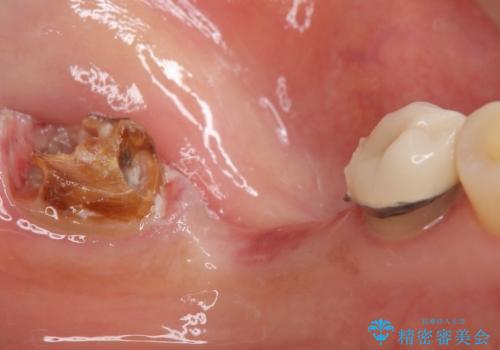

- 奥歯の痛みを主訴に来院された患者様です。

精査したところ、ブリッジの支台歯となっている左下の奥歯(左下7)は大きなう蝕により神経が死んでいました。

根管治療後、メタルボンドブリッジによる補綴治療を行いました。